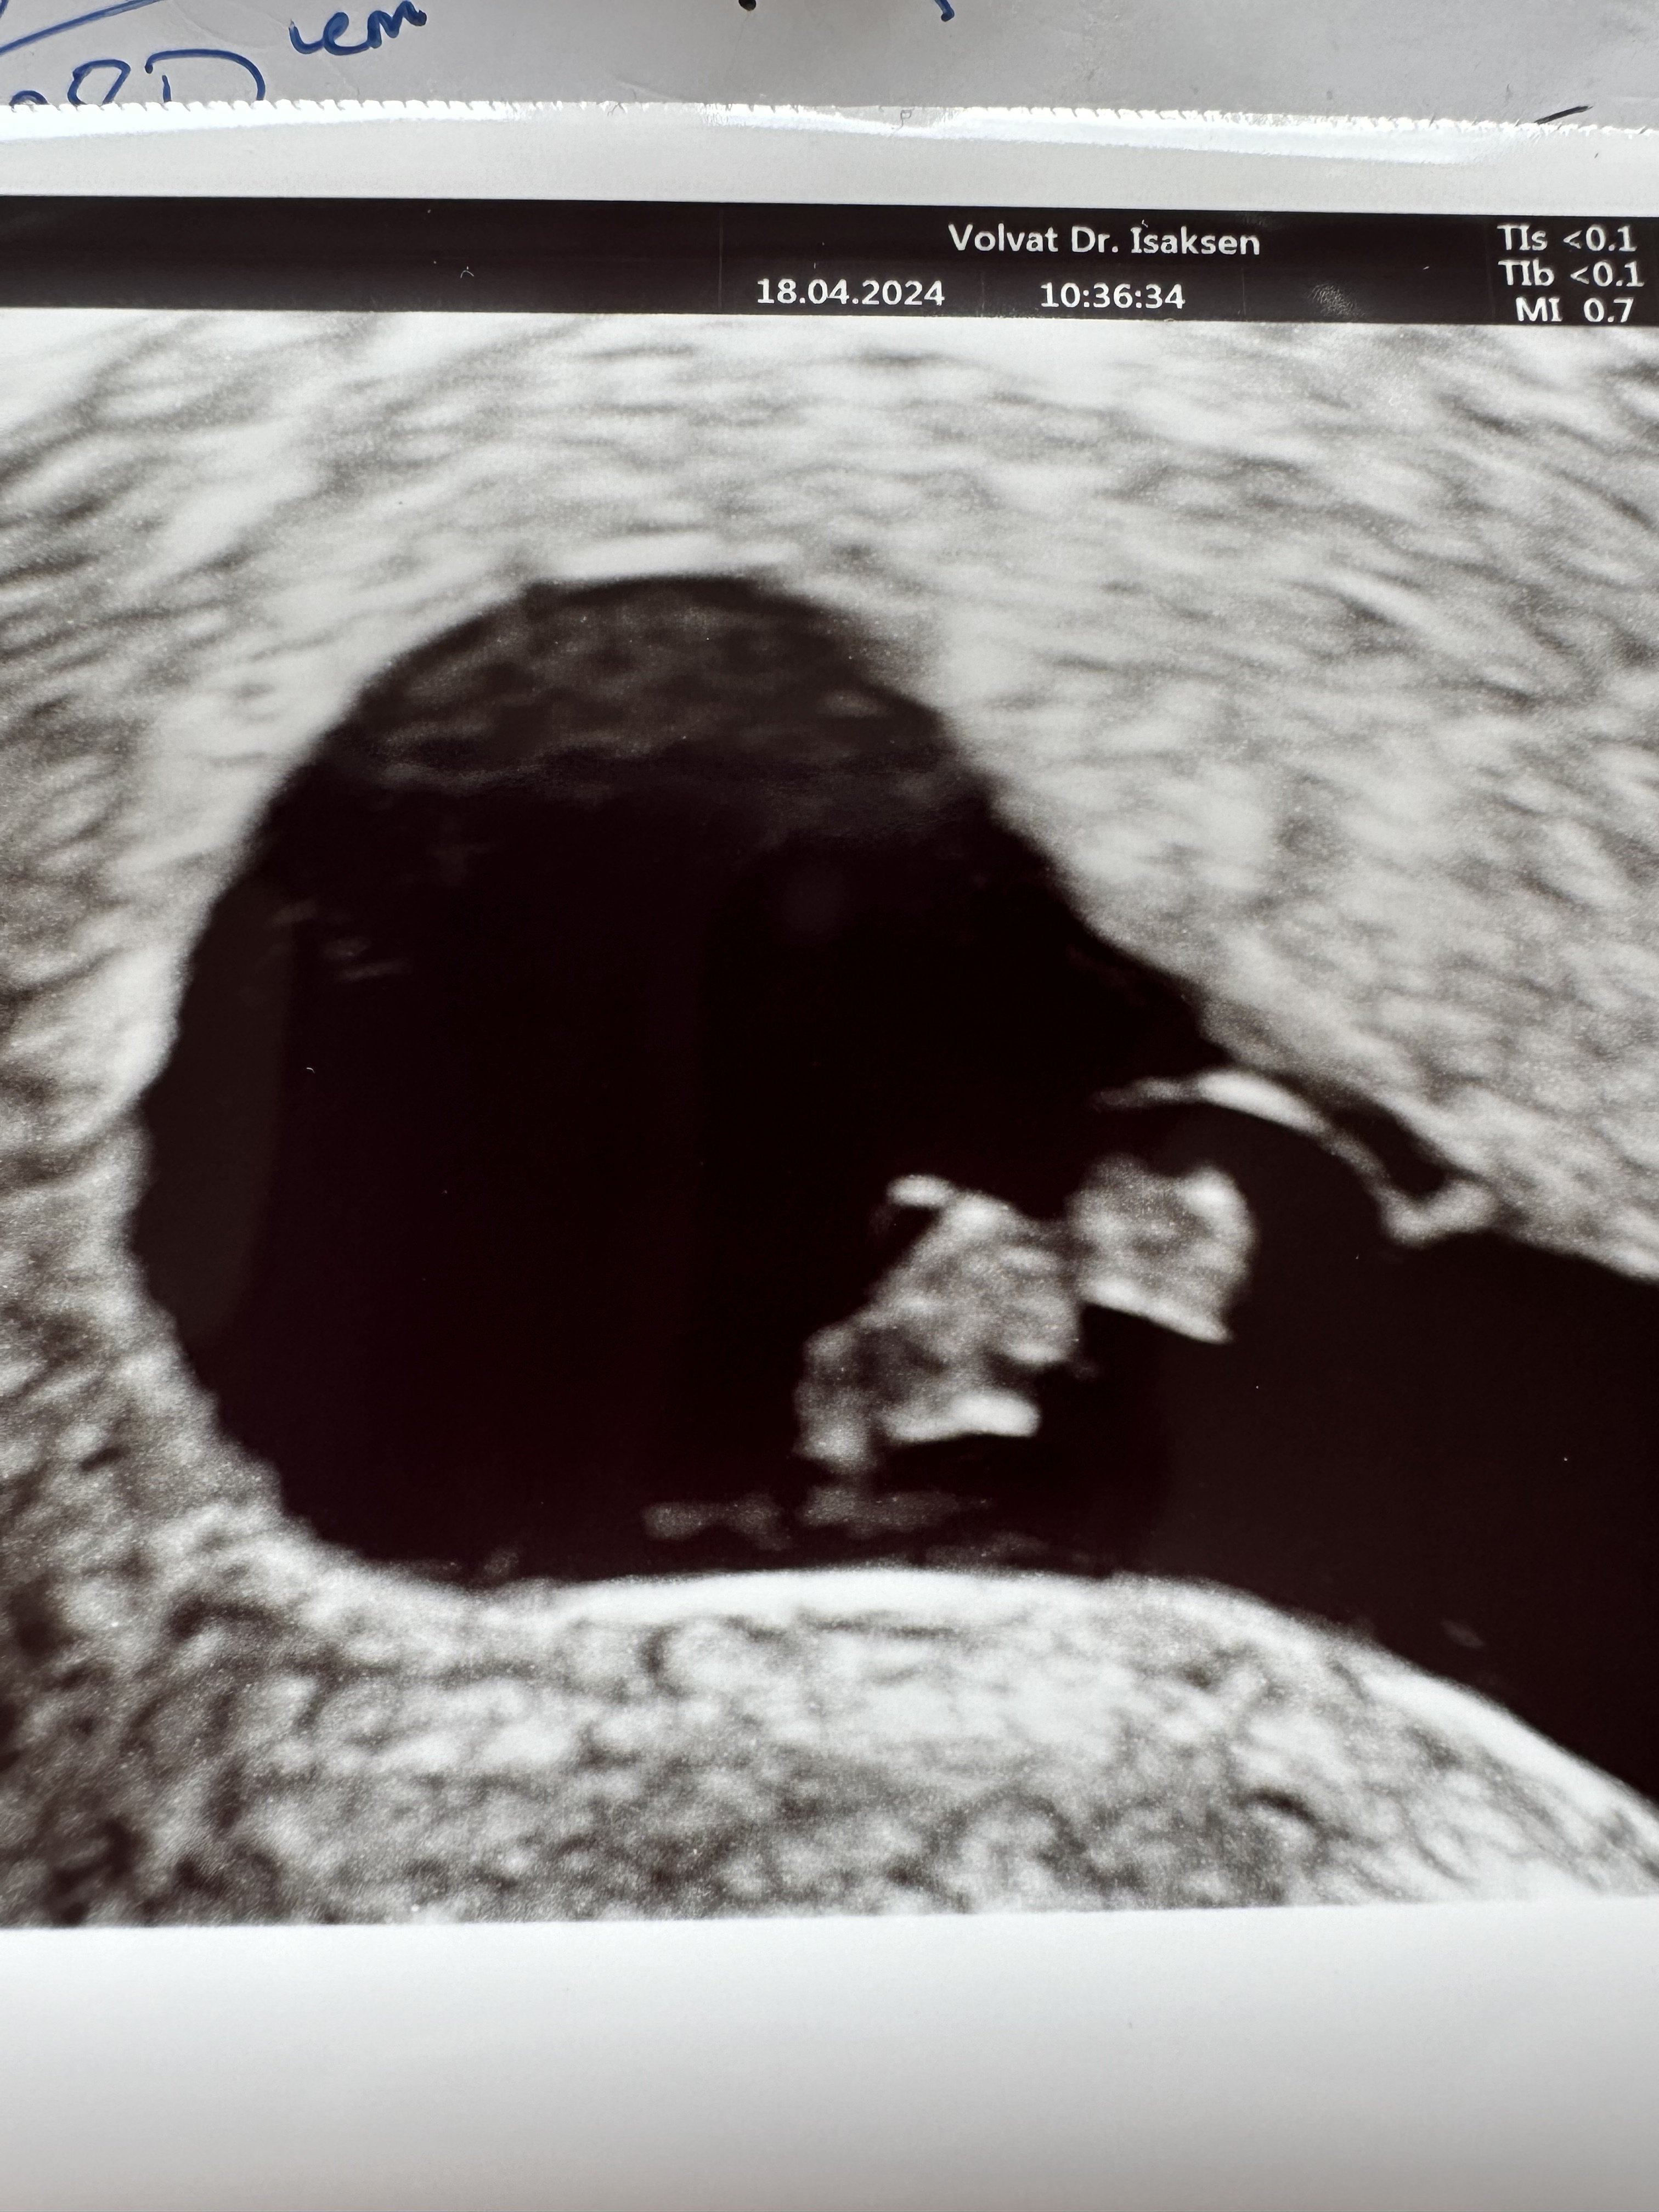

Lykke til!Her sitter jeg utenfor volvat, hele 15 minutter for tidlig til tidlig ultralyd

Hjertet hopper snart ut av brystet mitt. Jeg gruer meg, er spent og nervøs samtidig. Æsj

Hjertet banker og alt ser fint ut.

Så godt å se at alt står bra til!Det gikk braHjertet banker og alt ser fint ut.

Ble målt litt mindre på vei enn antatt (ei ukes tid) men forholder meg til menstermin til neste UL i det offentlige, så vil det jo bli fastsatt da. Spiller ingen trille uansett. Jeg lager jo små babyer så kan jo hende det er feil